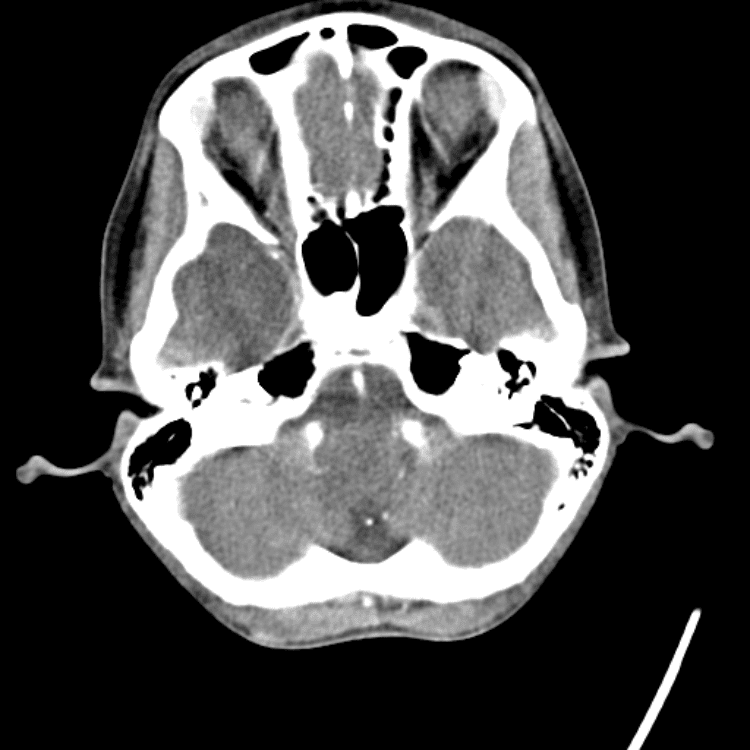

Head and Neck

Practice

Simulates call by including subtle or difficult cases and some normals.

27 cases